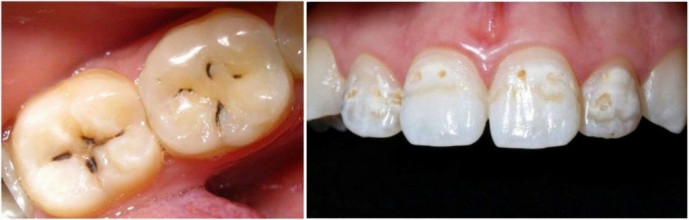

- Кариес в стадии белого/темного пятна (рис.1) –

в этом случае дефекта на поверхности эмали еще нет, но присутствуют пятна белого (иногда темного) цвета, которые говорят о том, что эмаль зуба потеряла много кальция в этих участках. Такая форма кариеса лечится не пломбированием, а путем реминерализации – насыщением эмали кальцием и фтором